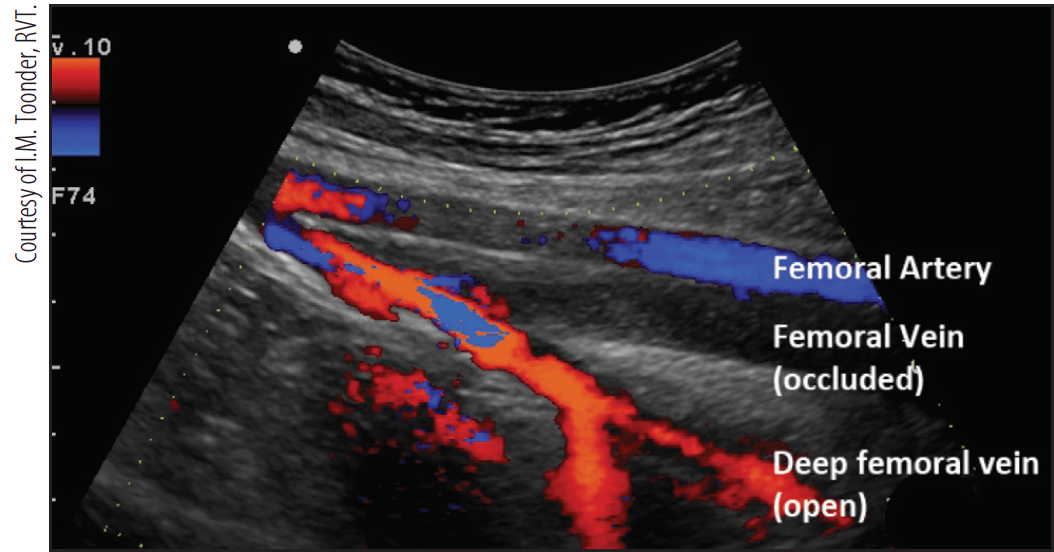

Der Duplex-Scan ist eine nicht-invasive Untersuchungsmethode, die Ultraschall verwendet, um den Blutfluss in den Arterien und Venen zu visualisieren und zu analysieren. Durch die Kombination von B-Bild-Sonographie und Doppler-Sonographie liefert er detaillierte Informationen über die Gefäßstruktur und die Blutflussgeschwindigkeit. Die Untersuchung spielt eine entscheidende Rolle bei der Diagnose verschiedener Gefäßerkrankungen.

Diese moderne Diagnostikmethode ermöglicht es Ärzten, Engstellen, Verschlüsse oder andere Anomalien in den Blutgefäßen zu erkennen. Dies ist wichtig, um Erkrankungen wie Thrombosen, Arteriosklerose oder Krampfadern frühzeitig zu diagnostizieren und entsprechend zu behandeln.

Ein Duplex-Scan ist eine bildgebende Untersuchung, die den Blutfluss in den Gefäßen misst und sichtbar macht. Dabei wird eine Kombination aus herkömmlichem Ultraschall (B-Mode) und Doppler-Ultraschall verwendet. Der B-Mode liefert ein Bild der Gefäßstruktur, während der Doppler-Ultraschall die Geschwindigkeit und Richtung des Blutflusses misst.